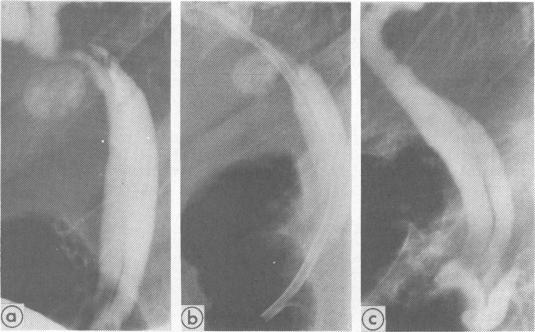

Saxne T, Wollheim F A, Pettersson H, Heinegård D

University Hospital, Lund, Sweden.

Br Med J (Clin Res Ed). 1987 Dec 5;295(6611):1447-8. doi: 10.1136/bmj.295.6611.1447.